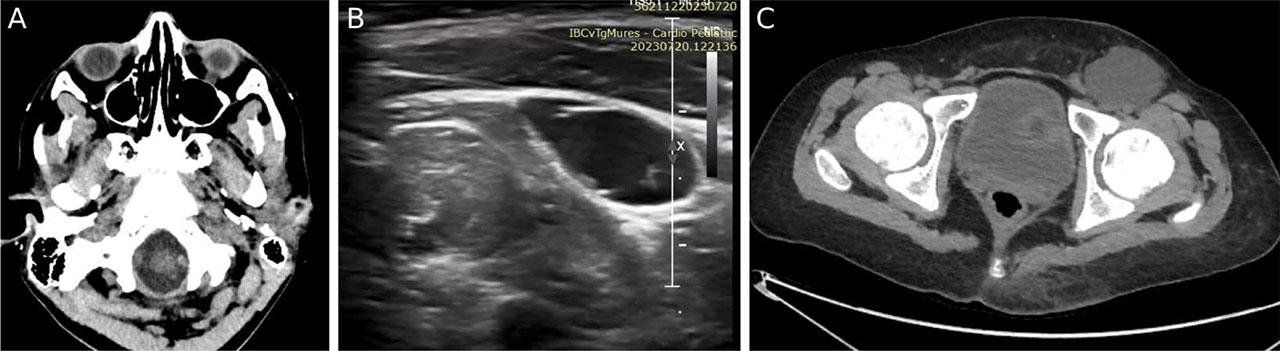

In the early follow-up, immediately after the heart transplant, he developed contractile dysfunction secondary to primary graft dysfunction (long ischemia time) and needed inotropic support (dobutamine 3 days, milrinone 16 days). The patient also developed new-onset neurological dysfunction with bulbar involvement: insomnia, apathy, muscle weakness, and swallowing and speaking dysfunction. Head computed tomography (CT) scan revealed hypodense image with hyperintense contour in the brain stem, interpreted as a bulbar ischemic injury (Figure 3A). He was treated with anticoagulants, vitamins and phenobarbital with slow, total remission of neurological symptoms. Moreover, Candida albicans colonization of the respiratory tract was revealed, and the patient received antifungal therapy with fluconazole.

Complications of VA-ECMO. A. Thromboembolic event: head CT scan revealing a bulbar ischemic stroke. B. Ultrasonic image of left inguinal seroma. C. Pelvic CT scan revealing a large, thin-walled left inguinal collection.

Two weeks after the heart transplant, a fluctuant collection became visible in the left inguinal region. Ultrasound and CT imaging revealed a large, thin-walled fluid cavity, suggestive for seroma (Figure 3B,C). It was drained by two needle puncture aspirations, but with recurrence. Hence, a surgical excision with hemostatic material was necessary, with total remission of the seroma afterwards. The patient also developed venous thrombosis at multiple sites (right jugular vein, left subclavian vein). In this context, thrombophilia testing was performed, which revealed heterozygote mutation for the MTHFR and PAI-1 genes. Anticoagulant treatment with heparin was initiated, which was later changed to enoxaparin and then to apixaban, with resolution of the thrombi.